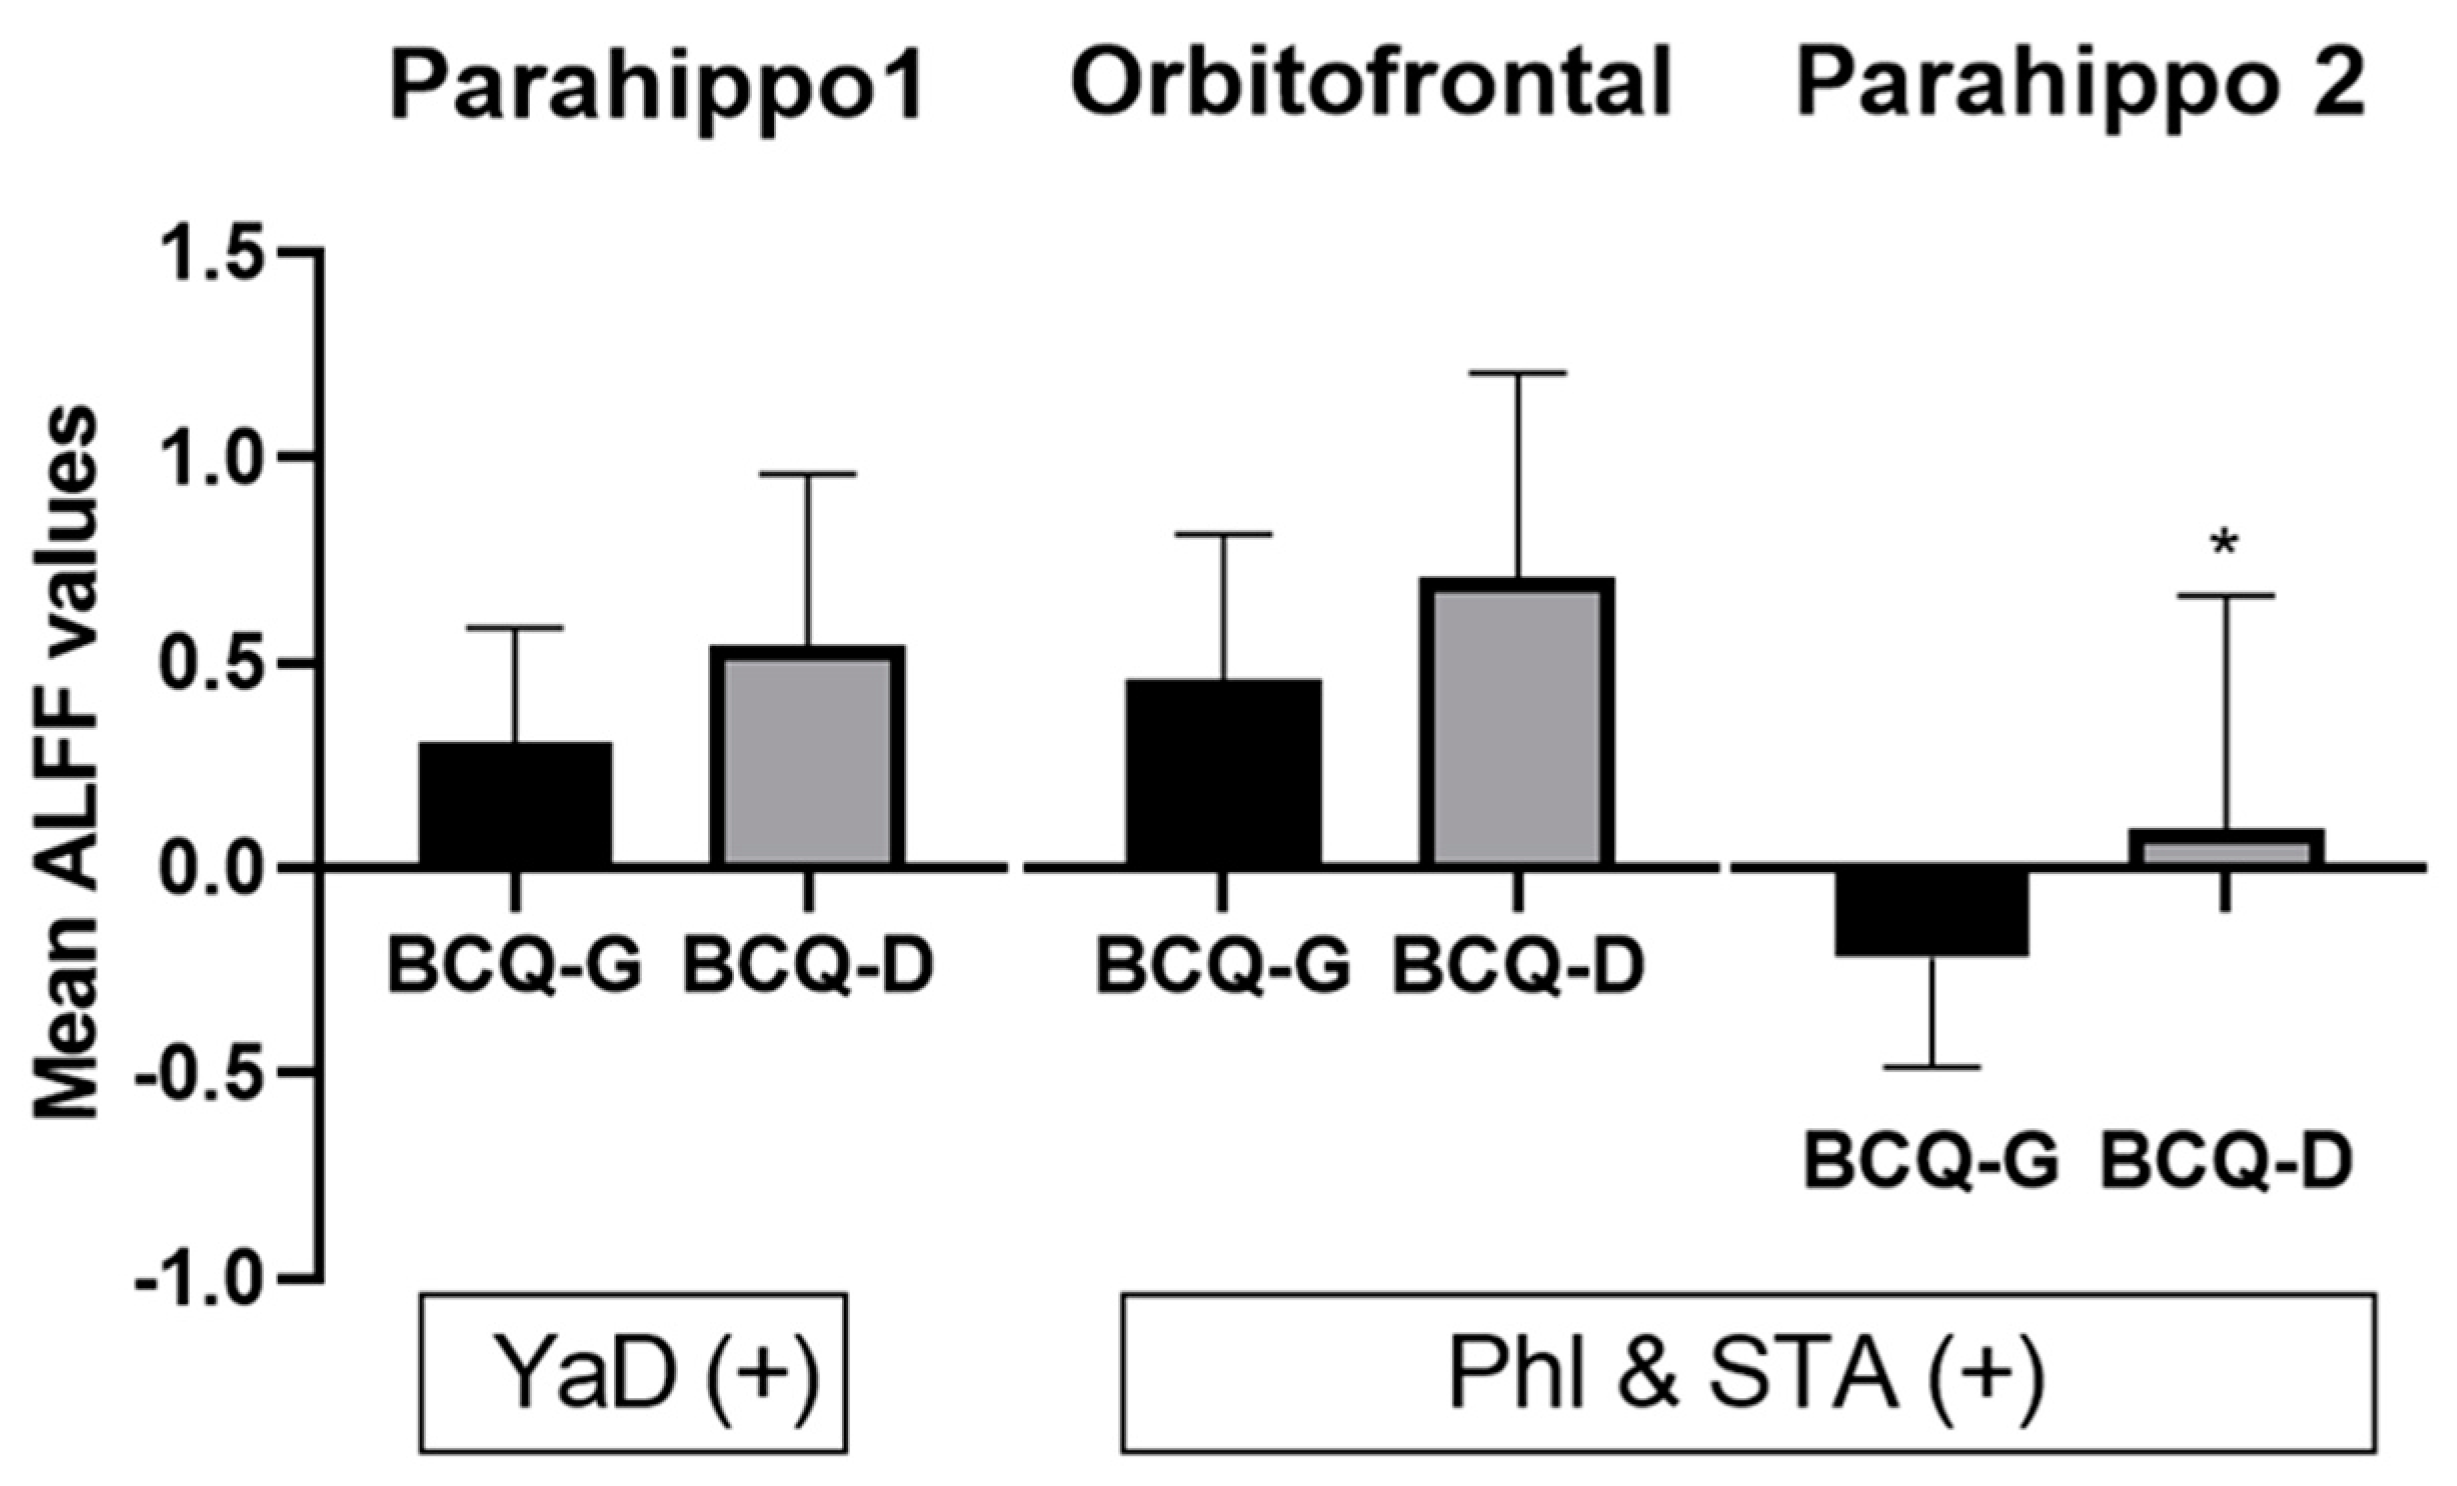

3.4. Correlation Analysis

| ALFF | |||||||

| Yang-deficiency | |||||||

| Positive | Parahippocampus, L | 36 | 289 | 4.32 | −21 | −18 | −24 |

| Phl & STA | |||||||

| Positive | Parahippocampus, L | 36 | 207 | 5.05 | −24 | −6 | −42 |

| Orbitofrontal cortex, L | 11 | 304 | 4.52 | −3 | 33 | −15 | |